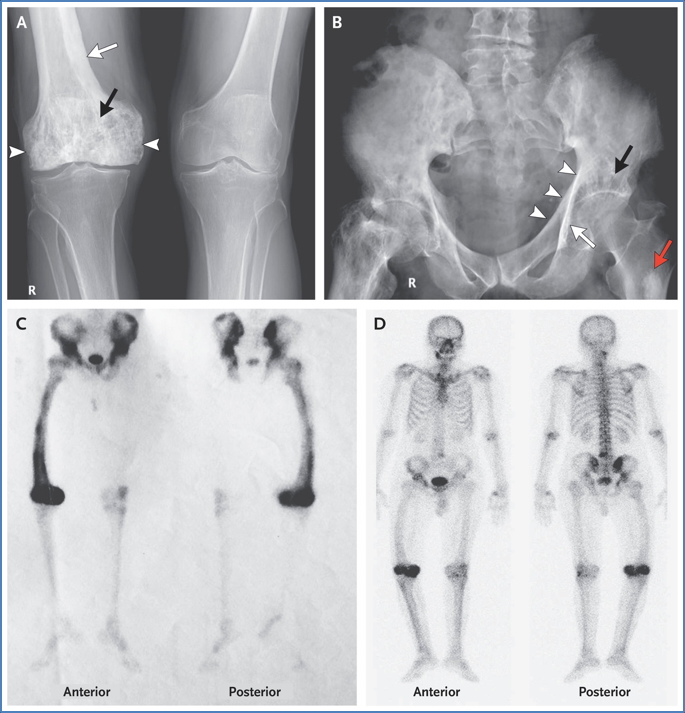

• X-ray:

• Mixed lytic and sclerotic lesions

• Advancing osteolysis in long bones or skull

• Compensatory osteoblastic activity → bone thickening